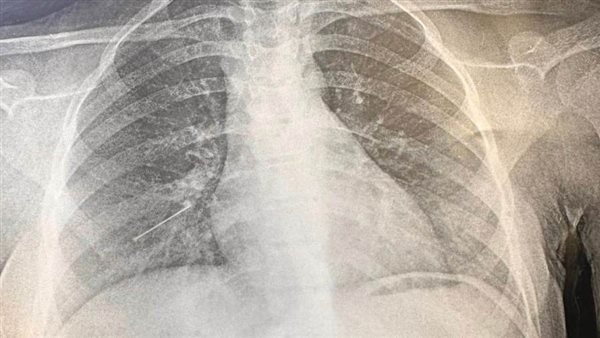

أما الحالة الثالثة فكانت جراحة صدر عاجلة لمريضة تبلغ من العمر 15 عاما تعانى من وجود جسم غريب "دبوس"، بالشعب الهوائية اليمنى البعيدة عن متناول المنظار الشعبي، وتم على الفور إجراء عملية جراحية واستخراج الجسم الغريب عن طريق شق صدري صغير محدود جدا وتم نقل المريضة للقسم الداخلى لاستكمال العلاج.